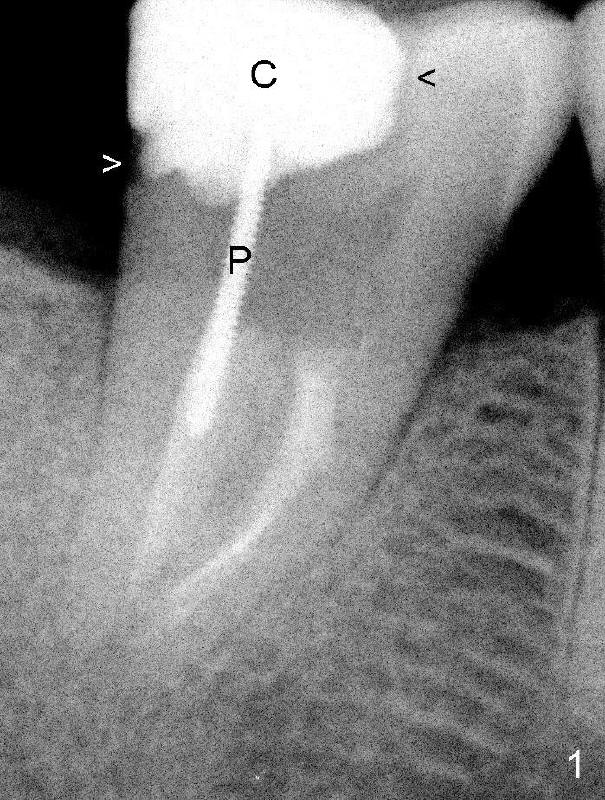

A 50-year-old lady presents to clinic with chief complaint "I need a new filling in the lower right". Root canal has been done in her home country without symptoms for several years. Exam reveals that the tooth #31 has DO composite. The mesial portion of the restoration has chipped (Fig.1: black arrowhead). There is 2nd caries in the distal margin (white arrowhead). Percussion reveals minimal tenderness. Crown is recommended. In addition to the post (P) and core (C), what is special about this case?

In fact, there is a separated file in the mesial canal (Fig.2: S). The related problem is that the mesial portion of the pulpal roof is not removed (arrowheads). The access to the pulp is limited (Fig.3: red lines), particularly to the mesial canal. The file must have been bent twice (pink line in an S shape) before separation. By comparison, the access to the pulp of another lower 2nd molar is sufficient (Fig.4 red lines) and the file is bent only once (pink line).